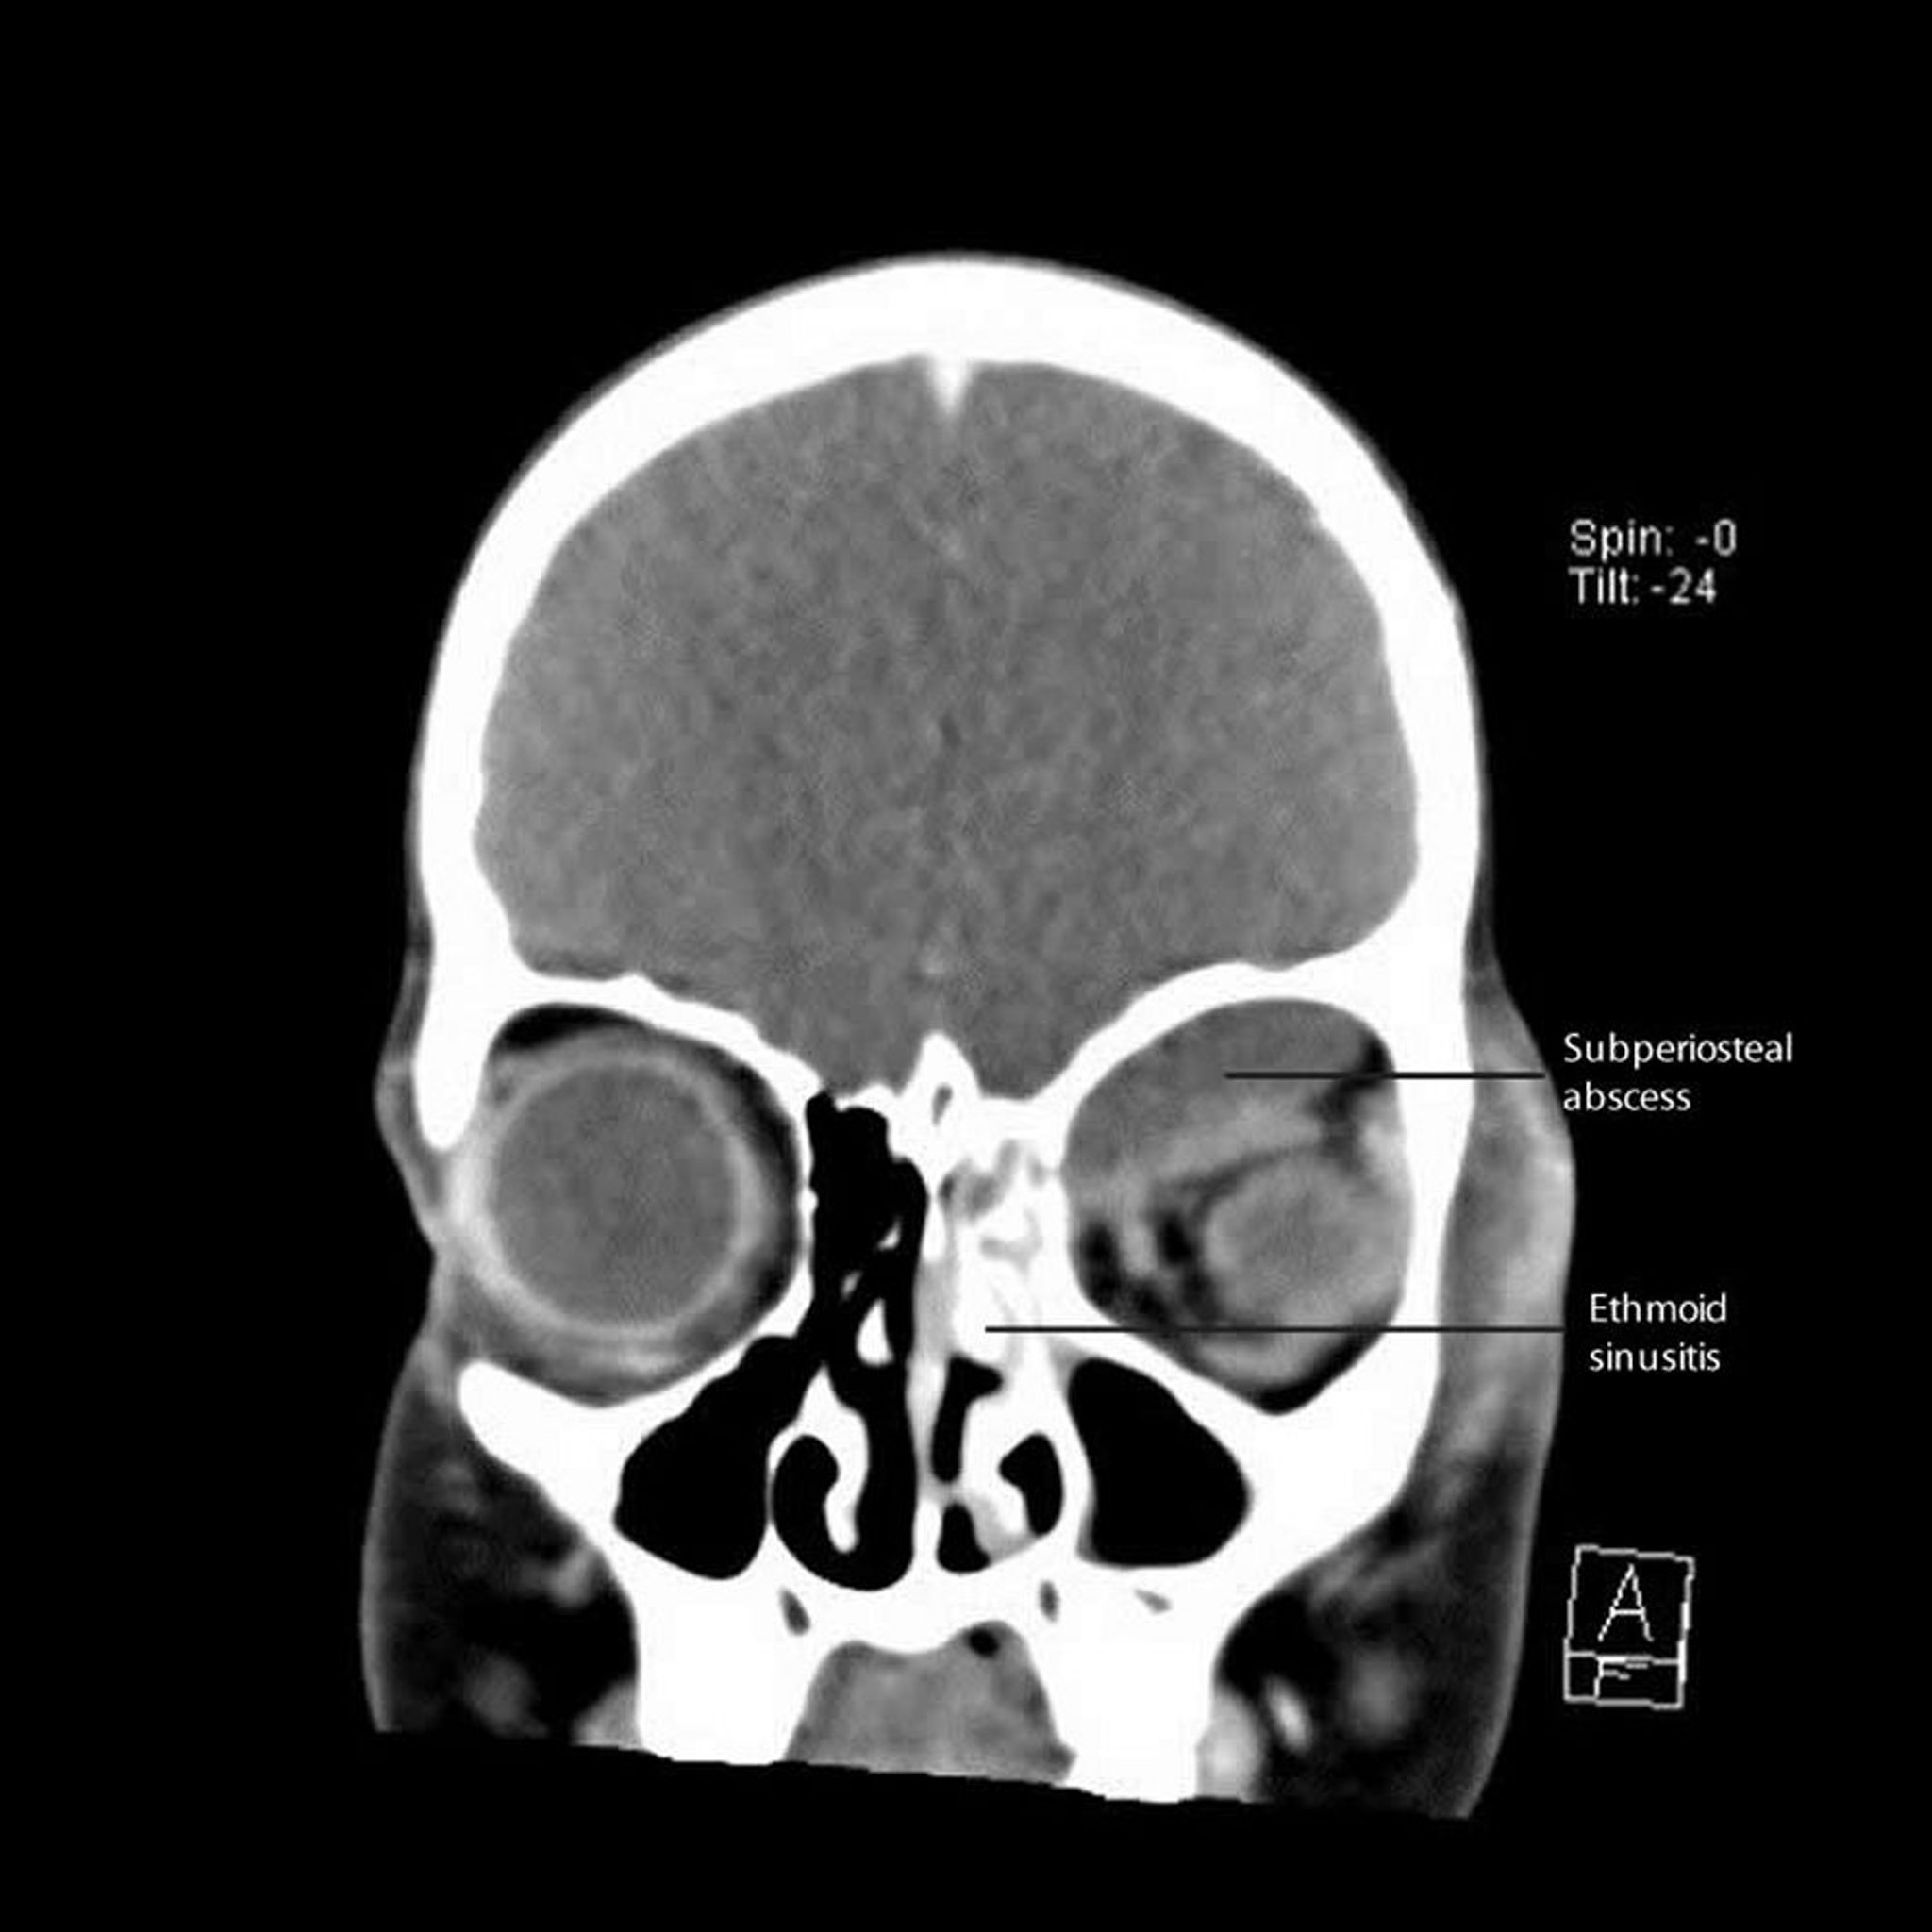

Sinusite etmoidale con ascesso sottoperiostale

Questa TC mostra una sinusite etmoidale sinistra con ascesso subperiostale adiacente lungo la parete mediana e il tetto dell'orbita.

CT courtesy of James Garrity, MD.